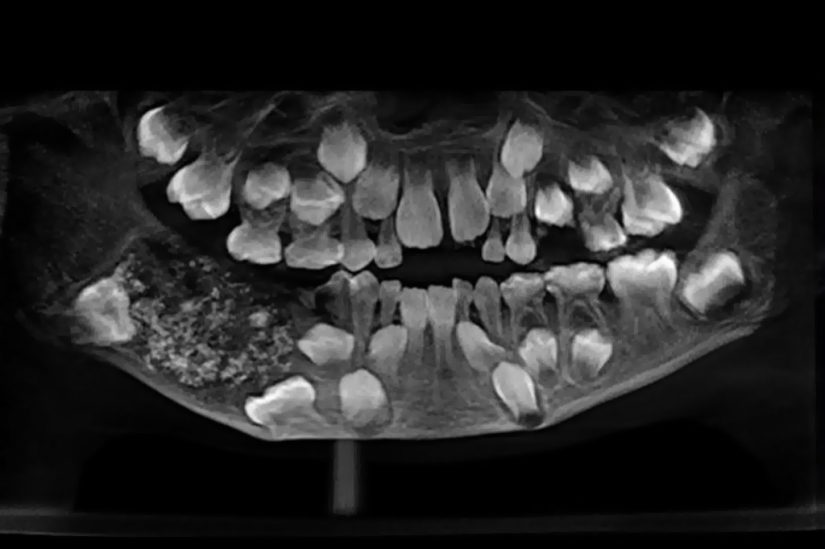

Para chegar a esse diagnóstico, os médicos fizeram o padrão: radiografaram todo o maxilar de Ravindranath. Quando examinaram a imagem, veio a surpresa: eles detectaram um saco (o tal do odontoma), embutido em sua mandíbula, cheio de “pontinhos” – que eram, nada mais nada menos, que “dentes anormais”.

Os odontomas são “tumores odontogênicos” que se localizam nas mandíbulas e se caracterizam por um crescimento lento e comportamento não agressivo. Geralmente eles são assintomáticos e detectadas por exames de rotina – se formam normalmente de resto de esmalte e dentina, que crescem de forma desordenada e podem se acumular.

Após a cirurgia para a extração do tumor, que pesava 200 gramas (!!!), os médicos precisaram de cerca de um mês para examinar individualmente todo o conteúdo do odontoma antes que pudessem confirmar suas descobertas

Agora, veio a confirmação: sim, dentro do odontoma haviam mais de 500 genuínos dentes, com coroa, esmalte e até raiz. Eles variavam de 0,1 milímetros a 15 milímetros. Segundo os médicos, este é o primeiro caso documentado no mundo em que em um indivíduo foi encontrado com tantos dentes minúsculos ao mesmo tempo.